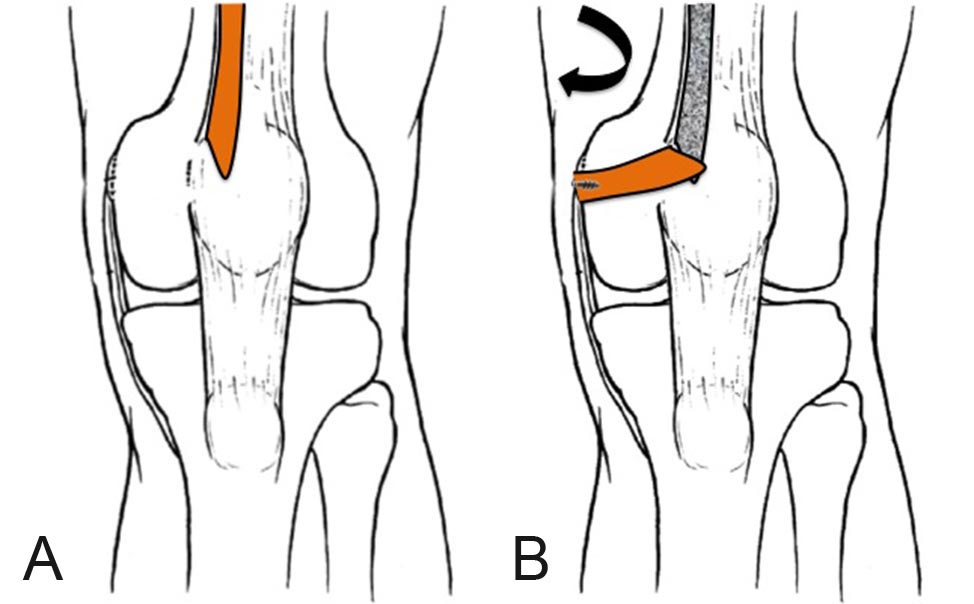

Figura 8: Diagrama de la técnica: A. Toma del injerto del tercio medial del TC, B. Fijación al punto anatómico en el fémur.

Steensen y cols.21 describieron la técnica que utiliza el tendón del cuádriceps (TC) para reconstruir el LPFM. La descripción original utiliza el tercio medio del tendón del cuádriceps (10-12 mm) dejando su inserción distal indemne y fijándolo el epicóndilo medial mediante con un tornillo interferencial. La desventaja de esta técnica es que el injerto no reproduce la inserción original en la rótula del LPFM. Noyes y Albright22 modificaron la obtención del injerto tomando el tercio medial (8-9 mm) del TC y la fijación femoral al utilizar suturas al septum intermuscular medial y refuerzos con puntos en 8 al retináculo medial.

En esta descripción modificamos el punto de inserción femoral, utilizando puntos de referencia radiográficos previamente descriptos7 y el método de fijación del injerto (Fig. 8). La utilización de puntos de referencia radiográficos permite identificar la zona exacta de inserción del LPFM original y restaurar anatómicamente esta estructura. La utilización de arpones permite una fijación más sólida y precisa que la que otorga la fijación con suturas.22 La utilización de tornillos interferenciales es una opción válida en pacientes esqueléticamente maduros pero en aquellos con fisis abierta, debido a la cercanía de la inserción femoral del LPFM con la fisis, tiene un riesgo mayor de lesionar esta estructura.